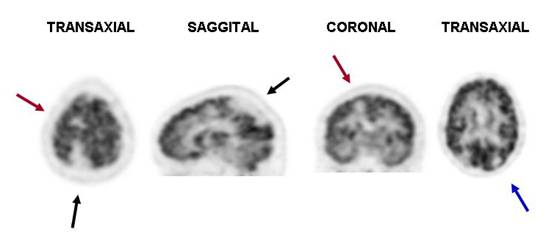

PET F18FDG Dose, 10 mCi, injected with glucose of 97 mg / dl.. Images show a large area of

decreased uptake of FDG in

right parieto-occipital lobes triangular shape and well defined edges (Black

Arrows). Additionally, there are two smaller areas, the first

high right parietal region at subcortical level (Red Arrows) and the second in the left

occipital area (Blue Arrow), both well-defined edges as well. The remaining brain scan, basal

ganglia and cerebellum with normaltracer distribution. Consistent with sequelae of vascular

events (infarcts).